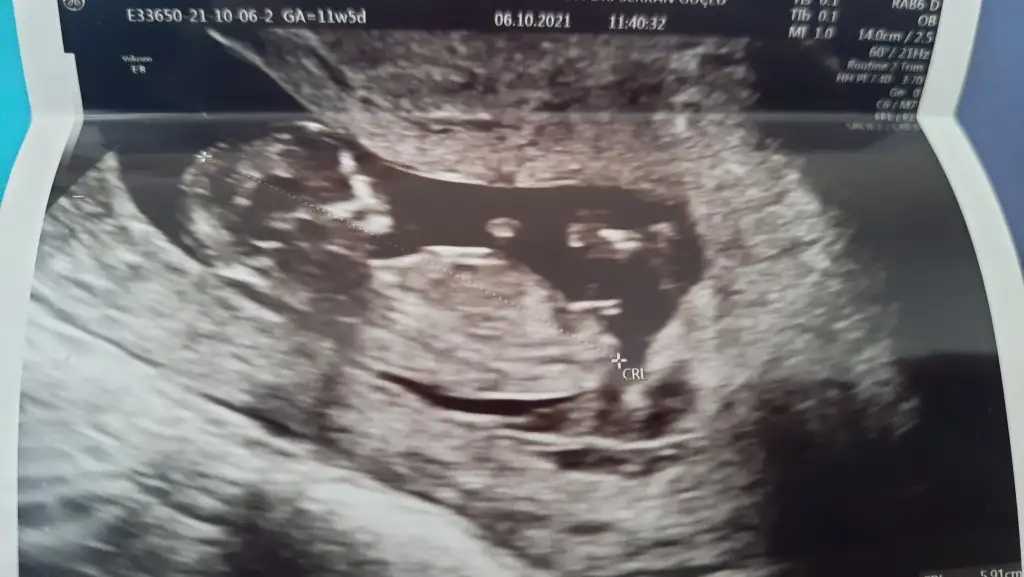

Emin olmadım sanki erkek gibiIkra meyra Merhaba, bu ultrason goruntuleri son adet tarihine gore 11+5, ultrason olcumune gore 12+3. Acaba cinsiyet icin bi yorum da bulunabilir misiniz ? Simdiden tesekkur ederim.

Emin olmadım başka USG varsa paylaşın sanki erkek gibi ama emin değilimIkra meyra rica etsem benim bebeğimi de tahmin eder misiniz 11+5